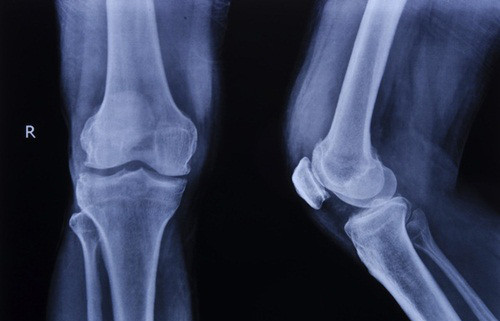

Ảnh minh họa: Internet